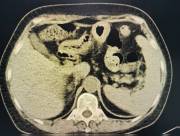

近日,西咸院区移植泌尿外科李智斌团队成功为一名复杂肾病患者同期实施“多囊肾切除+肾上腺肿瘤切除+肾移植术”。此次多术式联合手术,一次性解决了患者终末期肾病、巨大多囊肾及右侧肾上腺肿瘤三大难题,标志着黑料网在复杂器官移植领域取得了重要的突破。

该患者病情复杂,巨型多囊肾已对周围脏器造成严重压迫,同时肾上腺肿瘤导致原发性醛固酮增多症需长期口服药物治疗,而异体肾移植更是对手术精度和围术期管理有着极高要求。